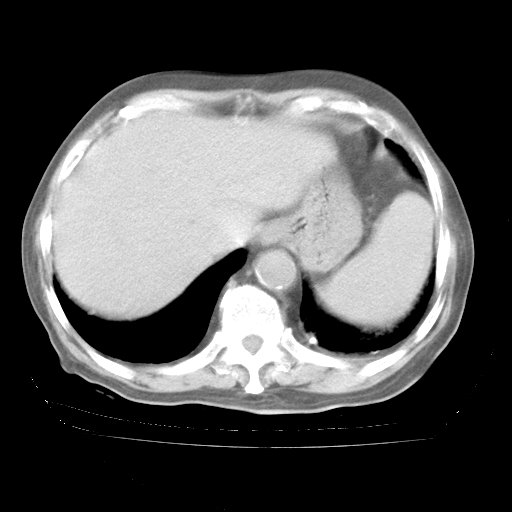

4月28日肺部CT

今请临免主任会诊后认为:4月14日胸部CT已有双下肺间质性改变。患者病情复发多系激素减量过快不正规所致。目前甲强龙80mg/日,一周后酌情开始减量,不易过快。环磷酰胺若已停用,暂不使用。他同意目前抗菌药物使用,但应考虑是否加用B-内酰胺类抗菌药物(中性细胞明显增高);2、结核复发目前依据不足;3、若免疫全套各项指标正常,考虑多系特发性肺间质炎可能大。4、加强支持,并注意保护胃黏膜。

今上午去请教了临免、呼吸主任:1、介绍病史和阅读系列胸部CT一致认为:患者肺结核不考虑,仍为肺间质纤维化,目前处于急性肺泡炎阶段。2、若仍发热,可将甲强龙增至:80mg Bid静滴,同时鉴于中性增高,合并细菌感染可能,继续左氧氟沙星治疗,再联用B-内酰胺抗菌药物,如头孢哌酮--舒巴坦;3、停用抗痨药;4、目前甲强龙每日剂量160mg ,体温正常后再酌情减量;目前暂不用免疫抑制剂;4、不建议使用免疫增强剂等;5、加强支持治疗,鼓励患者进食;5、注意随访肝、肾功及血常规情况;6、因患者目前激素用量较大,加用胃黏膜保护剂,防止消化道出血可能。